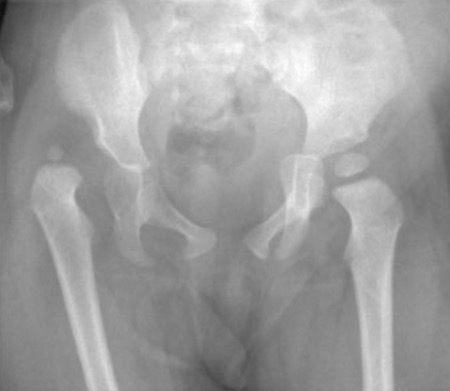

Chiari osteotomy